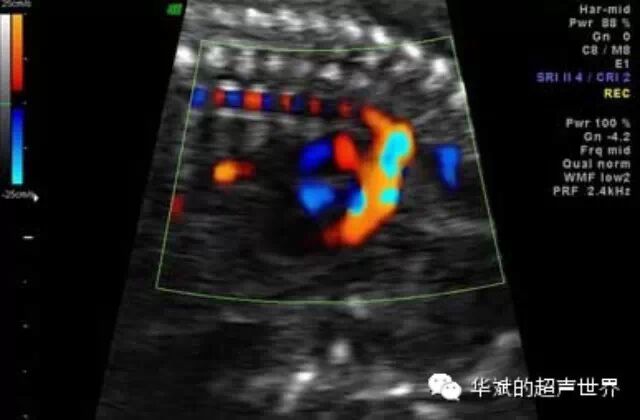

我们之前还讲过一个例子,胎儿的主动脉在彩色多普勒超声检查时有时会出现红蓝相间的现象,这也是声束经过胎儿椎体时发生折射所致,也是一种折射伪像(点击右边查看:昨日有奖问答答案)。

图4 声束折射导致胎儿的主动脉在彩色多普勒超声检查时有时会出现红蓝相间的现象。